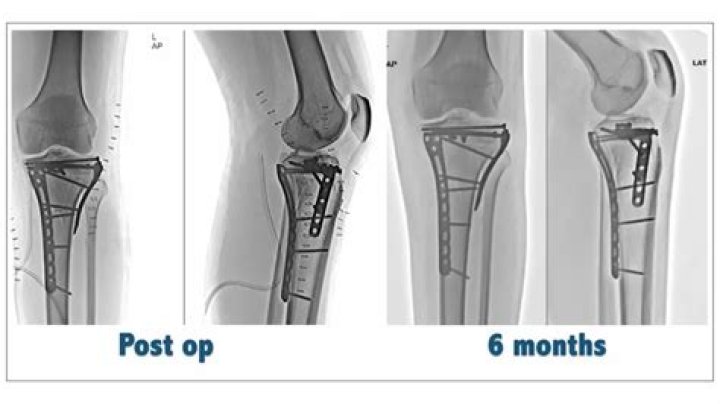

What is tibial plateau Orif?

Open reduction and internal fixation (ORIF) is the mainstay of most tibial plateau fractures, with the aim to restore the joint surface congruence and ensure joint stability. Any metaphyseal gaps can be filled with bone graft or bone substitute.

Partially articular factures can be treated by minimally-invasive methods and arthroscopy is useful to assist and control the fracture reduction and to treat intra-articular soft-tissue injuries. Open reduction and internal fixation (ORIF) is the gold standard treatment for these fractures.